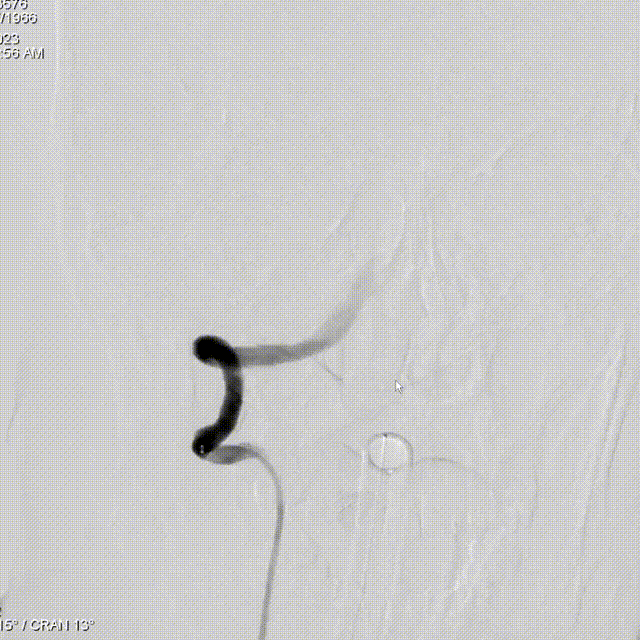

Lattice完全释放:

完全释放支架解脱。

造影显示整体打开贴壁良好。

术后即刻造影: